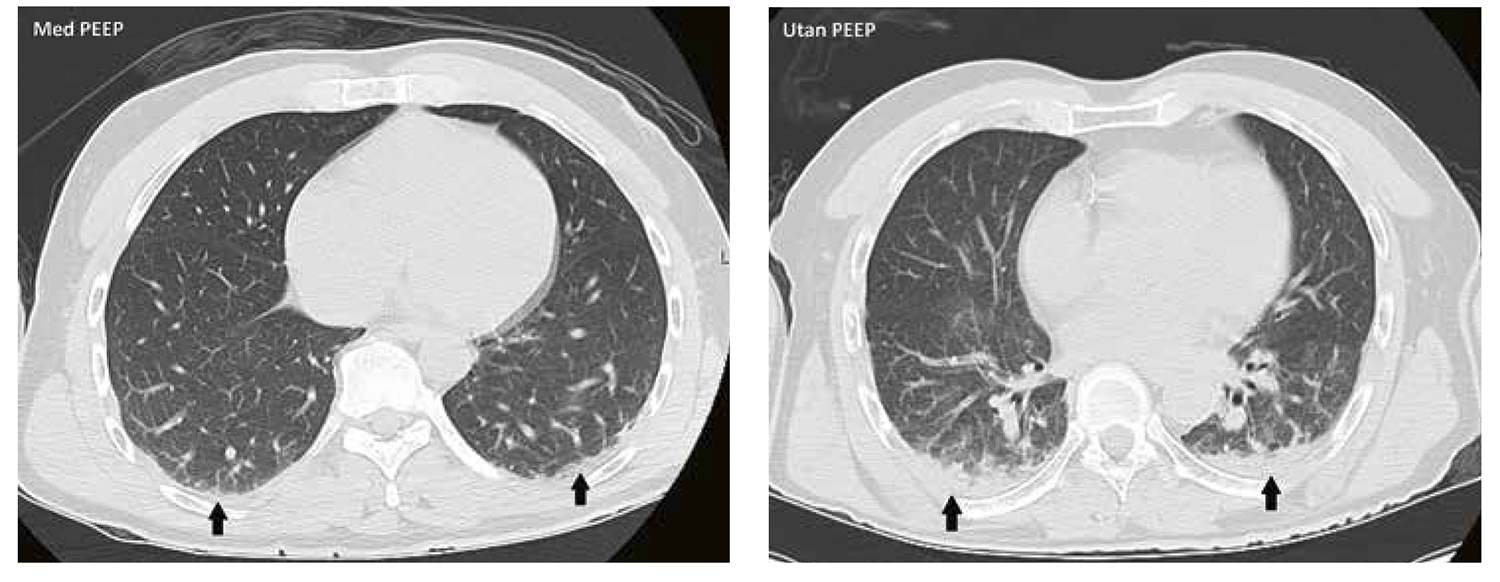

Atelektaser under anestesi – så kan de uppkomma och motverkas